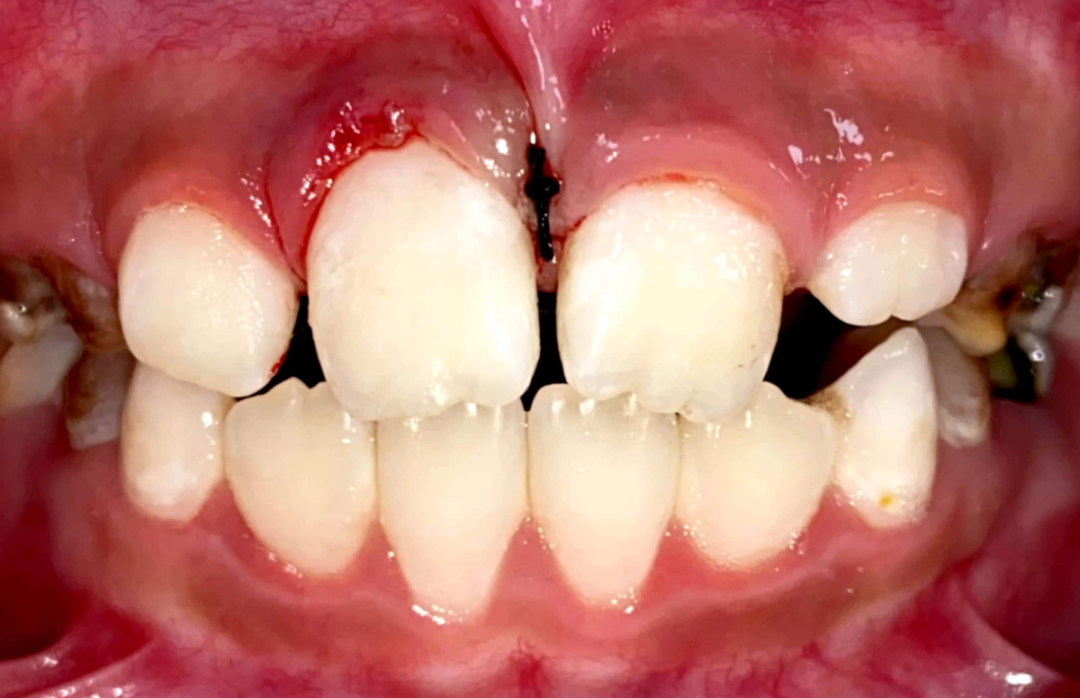

1、影响颅颌面发育:在儿童生长发育过程中,错颌畸形如不及时治疗,就会影响儿童口腔及面部软硬组织的正常发育。例如下牙列位于上牙列外侧,就会妨碍上牙列和上颌骨向前正常发育,导致面中部发育不足,即地包天。

2、危害口腔健康:排列不齐的牙齿,刷牙时不易清洁,使食物残渣长期滞留在牙间隙、牙龈边缘等处,容易发生龋齿(虫牙),牙龈炎(牙龈出血),严重者可发展为牙周病,造成牙齿松动甚至脱落。

4、影响面部美观:如果牙齿不整齐,微笑时会影响颜面美观,如开唇露齿,上颌前突,下颌前突,下颌后缩,长面型,短面型等都可引起面部不协调。

儿童错合畸形早期矫治是阻断影响儿童颌骨、牙齿正常发育的因素,促进颌面部正常发育,降低II期矫正的难度,减少II期矫正的时间,甚至不需要II期矫正。让孩子早期获得自信,绽放灿烂笑容。

术前→术后